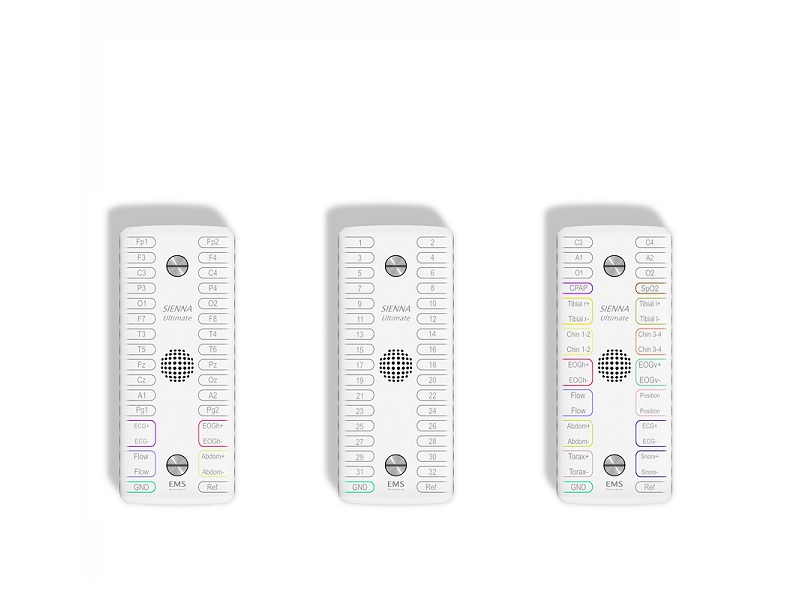

- NFB, BFB e qEEG – Neurobiofeedback

- EEG – Eletroencefalografia

- PSG - Polissonografia

- EMG – Eletromiografia

- CFM - Monitorização da Função Cerebral

- IOMN - Neuromonitorização Intraoperatória Neurofisiológica

- DTC - Doppler Transcraniano

- Neuromodulação

- fNIRS - Functional near-infrared spectroscopy

- Robo Exoesqueleto

- Biofeedback Reabilitação

- Gait Analysis